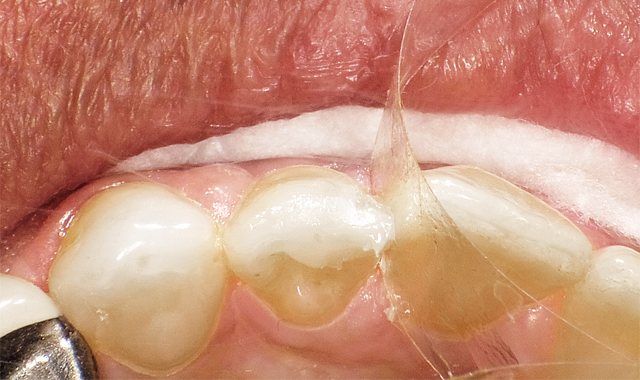

After placement of a bulk fill low stress flowable and again appropriate light curing, the final 2 mm of warmed A2 G-ænial Sculpt was placed in one bulk fill manner. After finishing and polishing, the above restoration truly maximizes tooth preservation (Fig. 3).

After finish and polishing, this restoration truly maximizes tooth preservation.